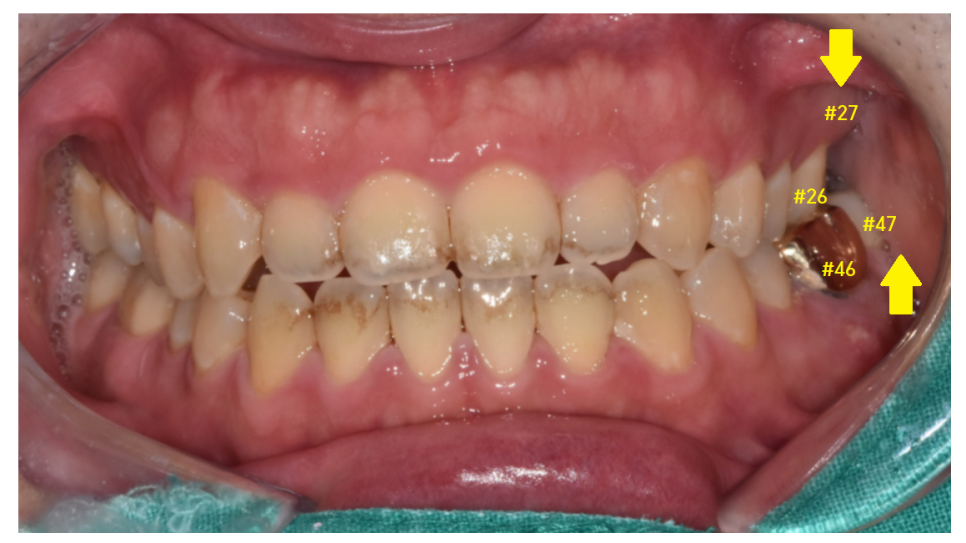

암사동 치과 환자분 사진을 함께 보실까요~?

- 윗니 맨 치아가 빠지고

아래 맨 끝 어금니가 물린다.

23.01.12

치아 개수가 하나가 비죠~?

오른쪽 맨 위 치아가 빠진 환자분입니다.

구강 내 사진을 보겠습니다.

23.11.04

#27 맨 끝에 치아가 부러졌네요~

발치가 필요합니다.

구강 내 사진에서도 이가 한 개가 없죠~?

교합되는 사진을 보겠습니다.

#27 왼쪽 맨 끝 치아가 상실

#47 왼쪽 아래 맨 끝 치아가 물리는 게 없네요~

이럴 경우 맞닿은 치아가 없어서

아래 치아가 위로 쑥쑥 올라오게 됩니다.

자연치아의 손상을 방지하기 위해서라도

임플란트가 필요합니다.